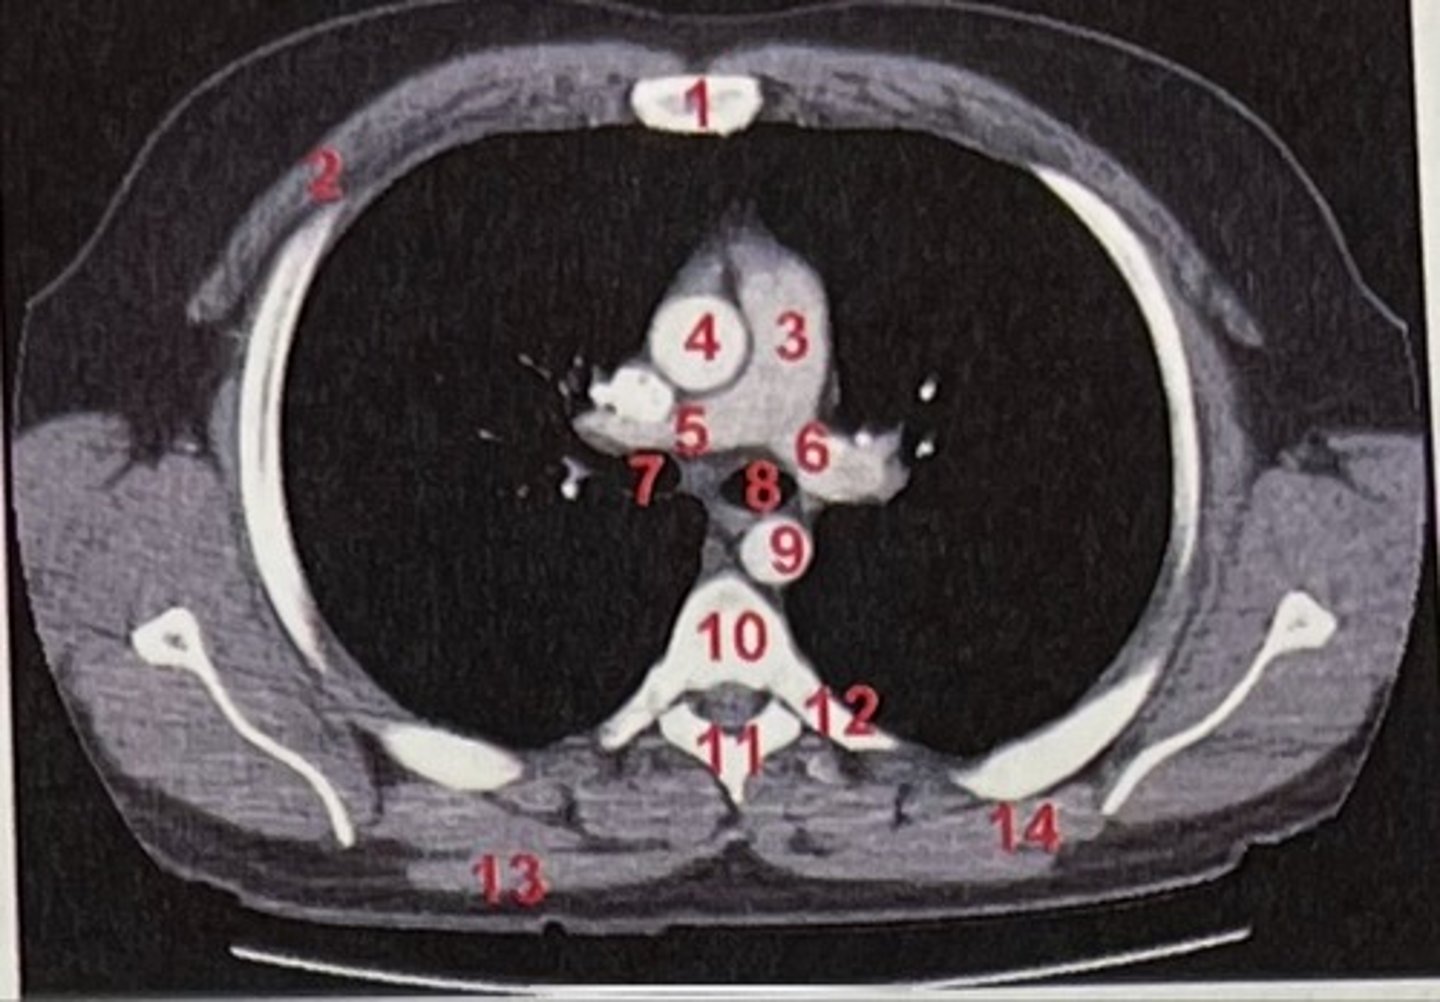

Sternum

What is 1

pectoralis major

What is 2

Pulmonary trunk

What is 3

Right and left pulmonary arteries

What is 5 and 6

Ascending aorta

What is 4

right primary bronchus, left primary bronchus

What is 7 and 8

Descending aorta

What is 9

Rhomboid major

What is 14